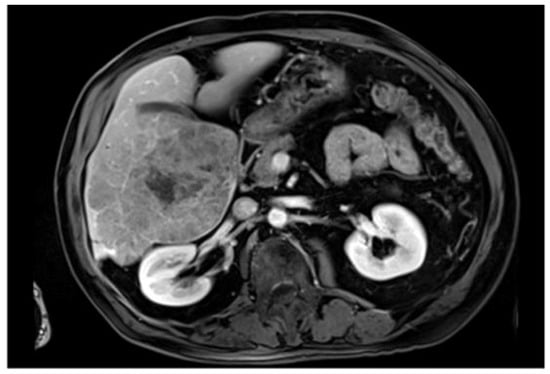

| 3DIRCADb | CT scans from 20 patients with annotations for liver and liver tumor segmentation | Detailed 3D reconstruction data aid the development of segmentation algorithms for complex liver structures | Small sample with limited case types |